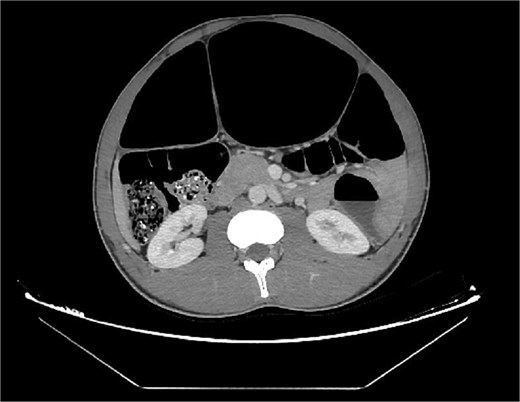

Abdominal radiography demonstrated classic features of sigmoid volvulus including dilated colonic loops, multiple air-fluid levels, and the characteristic coffee bean sign with absence of rectal gas. Computed tomography (CT) imaging (Figs 1 and 2) confirmed the diagnosis, revealing large gas-filled loops (maximum diameter 100 mm) without haustration and the typical mesenteric whirl sign, consistent with closed-loop obstruction. Initial management with colonoscopic decompression was attempted but proved unsuccessful, with persistent abdominal distension and tympani necessitating surgical intervention. Intraoperative findings confirmed a dolichosigmoid with mesenterico-axial volvulus, requiring sigmoid colon resection with creation of a double-barrel stoma using the Bouilly-Volkmann technique. Pathological examination of the resected specimen (30 cm in length, 491 g in weight) revealed flattened, hemorrhagic mucosa with vascular congestion and edema (Fig. 3). Microscopic analysis identified numerous Schistosoma eggs of varying morphology (Fig. 4A and B) within the submucosa and muscular layers, accompanied by granulomatous inflammation (Fig. 4C) and dense eosinophilic infiltrates. Chronic changes including eosinophilic microabscesses and calcified eggs were also noted (Fig. 5).

(A) The preliminary view on abdominal CT (scout view) revealed a distended sigmoid loop exhibiting an inverted U-shape, commonly recognized as the coffee bean sign. (B) The preliminary view on abdominal CT (scout view) showed dilated bowel loops.

Axial abdominal CT scan revealed dilated gas-filled loops with lack of the haustration.